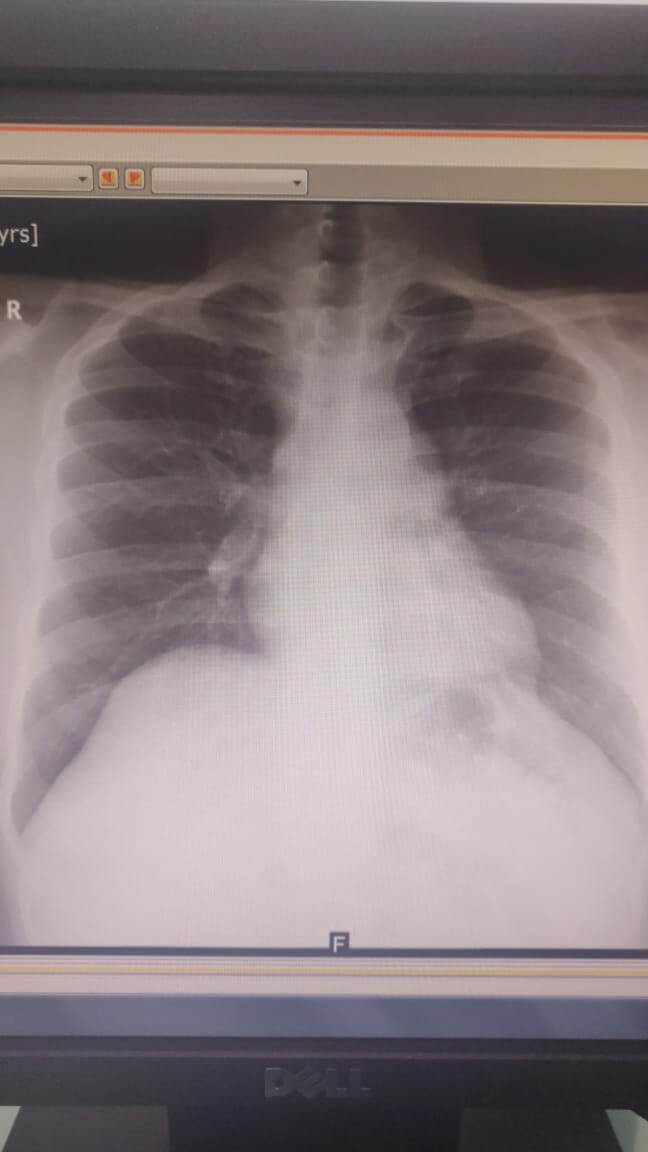

A 31-year-old male patient had incidental finding of left mediastinal mass during occupational screening.

The patient’s CT showed cystic mass. Robotic left mediastinal tumor excision was planned. On table, cystic mass was confirmed as pericardial cyst and excised. The patient was discharged on the second day after operation and resumed work in a week.